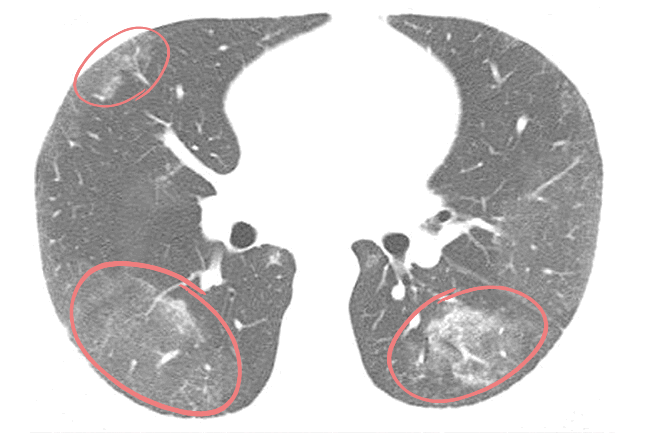

Оценивая данные КТ легких, врач-рентгенолог дифференцирует заболевания по специфической картине «матовых стекол»: их количеству, локализации, наличию других признаков, по которым возможно определить причину патологических изменений ткани легких. Например, для двусторонней вирусной пневмонии характерно наличие «матовых стекол», расположенных периферически в нижних и задних отделах легких. В более поздней стадии наблюдается консолидация очагов инфильтрации с утолщением перегородок альвеол.

Общим признаком острых пневмоний на КТ является наличие инфильтратов («матовых стекол») разной формы и протяженности. «Матовые стекла» расположены вокруг очагов или диффузно, как при туберкулезе. Однако в отличие от туберкулеза, их размер обычно больше, есть тенденция к консолидации инфильтратов и образованию рисунка по типу «булыжной мостовой». В отдельных случаях визуализируются просветы бронхов, содержащих газ. Это называется синдромом «воздушной бронхографии». В сочетании с эффектом «матового стекла», он также относится к явным признакам пневмонии.

Для пневмонии, вызванной коронавирусом COVID-19, характерно периферическое расположение очагов поражения под плеврой. Наиболее уязвимы билатеральные нижние доли и задние отделы легких. Отмечается тенденция к консолидации «матовых стекол» и утолщению перегородок альвеол, иногда — признаки фиброза легких.

Тяжелым формам коронавирусной пневмонии сопутствует острый респираторный дистресс-синдром. ОРДС — это обширное двухстороннее воспаление, при котором наблюдается множество инфильтратов и отек легких. На томограммах фрагментарные участки «матового стекла» кортикальной формы присутствуют с двух сторон и имеют вид «лоскутного одеяла».

При пневмоцистной пневмонии, вызванной дрожжеподобным грибом Pneumocystis Jirovecii, наблюдается несколько иная картина. Участки уплотнения легких по типу «матового стекла» обычно расположены с двух сторон симметрично (но иногда диффузно и неравномерно). Уплотнения преобладают в прикорневых областях легких, а диффузные изменения — в верхних и нижних отделах. Для пневмоцистной пневмонии, как и для вирусной, ассоциированной с COVID-19, характерны эффект консолидации и симптом «лоскутного одеяла», но на томограммах легких видны и другие признаки: воздушные кисты, пневмоторакс.